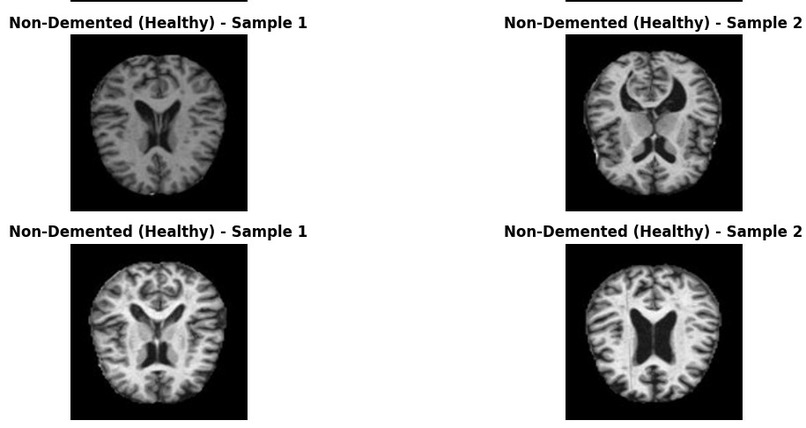

BrainGuard classifies brain MRI scans into four categories:

Glioma (brain tumor) Meningioma (tumor) Healthy (no disease) Pituitary (tumor)